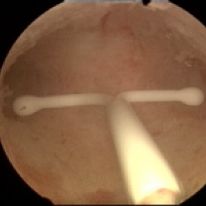

Frameless copper IUDs are designed to optimize intrauterine contraception The uterine cavity width is the most important parameter relate...

Read moreIn his clinic in Ghent, Dr. Wildemeersch organizes training sessions for doctors from inside and outside Belgium, interested in learning the anchoring technique of frameless intrauterine devices.